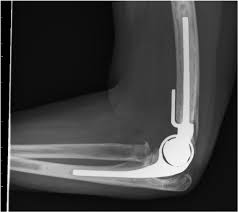

Conditions Mr Treseder treats frequently include fractures and dislocations of the upper limb and lower limb, deformity correction, joint problems and arthritis.

elbow reconstruction protocol

Shoulder Replacement Protocol